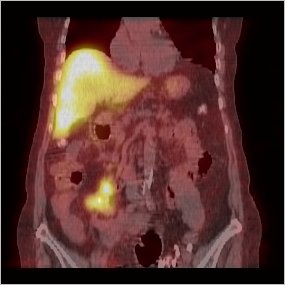

/ Obr. č. 5: Fúze obrazů SPECT a CT. Zaměřeno na ložisko v pravém mesogastriu. Řez transverzální, sagitální a koronární. Vyšetření 24 hod. po aplikaci OctreoScanu.

/ Obr. č. 6: Fúze obrazů SPECT a CT. Zaměřeno na ložisko v pravém mesogastriu. Řez transverzální, sagitální a koronární. Vyšetření 24 hod. po aplikaci OctreoScanu.

/ Obr. č. 7: Fúze obrazů SPECT a CT. Ložisko v pravém mesogastriu. Řez transverzální. Vyšetření 24 hod. po aplikaci OctreoScanu.

/ Obr. č. 11: Fúze obrazů SPECT a CT. Ložisko v pravém mesogastriu. Řez koronární. Vyšetření 24 hod. po aplikaci OctreoScanu.

Dochází k fyziologické depozici radioaktivity ve slezině, v obou ledvinách, játrech, močovém měchýři, jen lehce ve střevech. Dále jsou za 4 a 24 hod. patrná dvě splývající patologická ložiska zvýšené depozice radioaktivity v pravém mesogastriu promítající se do střev.

Závěr: dvě splývající patologická ložiska zvýšené depozice radioaktivity v pravém mesogastriu promítající se do střev. Nález svědčí pro přítomnost tkáně se zvýšenou hustotou somatostatinových receptorů, v tomto případě jde zřejmě o primární tumor, karcinoid.

Lokalizací odpovídá nálezu na CT.